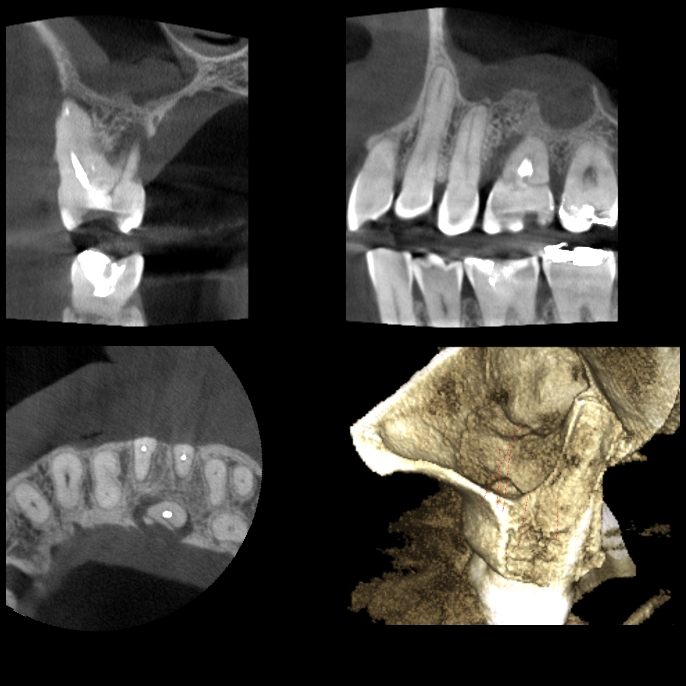

Estudios 3D

- Tomografía volumétrica con técnica de cone beam localizada.

- Tomografía volumétrica con técnica de cone beam para endodoncia. Cortes de 75 Mm

- Tomografía volumétrica con técnica de cone beam Hemiarcada.

- Tomografía volumétrica con técnica de cone beam completa

- Tomografía Bimaxilar